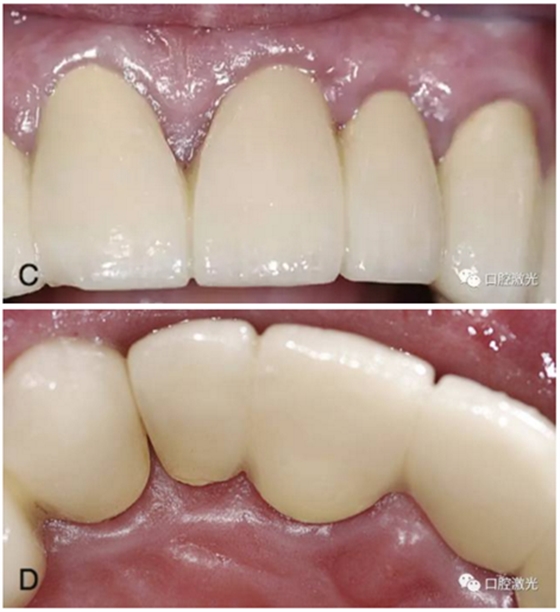

激光在牙冠延長(zhǎng)術(shù)中的應(yīng)用

隨著美學(xué)修復(fù)和保存修復(fù)的不斷發(fā)展,牙冠延長(zhǎng)術(shù)在臨床中的應(yīng)用越來(lái)越多。牙冠延長(zhǎng)術(shù)的目的是在符合牙周生物學(xué)寬度條件下暴露更多的健康牙體組織。